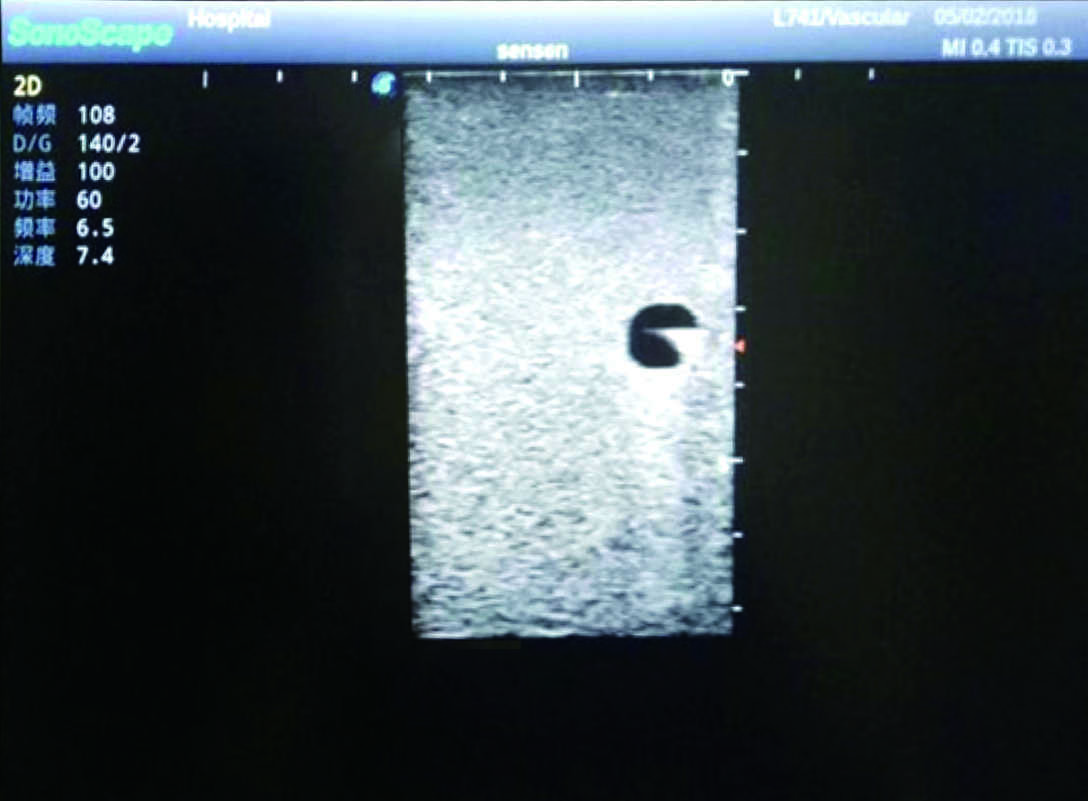

PICC Ultrasound Training Model

Model TYE1510.1

Outline

It is a model covering up from lobulus auriculae plane to the umbilical plane, and it has anatomical structures like clavicle, rib, sternocleidomastoid, jugular vein and basilic vein.

Features

1)   Made of high molecular polymer ultrasound material, close to the real skin

2)   It can be used by real ultrasound machines

3)   Clear and real images of the tissues and organs (basilic vein and superior vena cava)